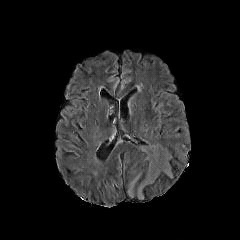

We use two popular medical imaging datasets primarily used for the evaluation of lesion segmentation: the Multimodal Brain Tumor Segmentation Challenge 2018 dataset (BratS18) [21, 2] and the Liver Tumor Segmentation Challenge dataset (LiTS).

BratS18.

The BratS18 dataset provides 210 high grade glioma (HGG) and 75 lower grade glioma (LGG) MRI with binary masks for the tumor (or lack of tumor). Each 3D MRI contains 155 slices of size 240×240240240240\times 240. Not every slice contains a tumor, and therefore healthy MRI are provided by this data as well. We use the FLAIR modality image for all the experiments because the entire tumor is represented well by this modality.However, we also show more experimental results on other modalities, where the ANT-GAN provides impressive visual quality. A more detailed medical description of the data can be found on the challenge website.111https://www.med.upenn.edu/sbia/brats2018.html

LiTS.

We also experiment with the LiTS data containing a total of 131 contrast enhanced abdominal CT volume images of the liver acquired from 7 different clinical institutions. The in-plane resolution ranges from 0.5mm to 1mm and the slice thickness ranges from 0.7mm to 5.0mm. Each slice is 512×512512512512\times 512 in size and we resize them to 256×256256256256\times 256, and as with the BratS18 MRI not every slice contains a lesion and so these slices are considered to be healthy images. A detailed data description can be found on the challenge website. 222https://competitions.codalab.org/competitions/17094

Aside from the difference in imaging tissue and modality of these two data sets, the tumor regions on the CT images are of different shape and size, as can be seen in Figure 4. Also, many CT scans are acquired in a way that introduces greater noise-like artifacts than MRI. For each dataset, 80%percent8080\% of randomly selected data are used for training and the resting 20%percent2020\% for testing.